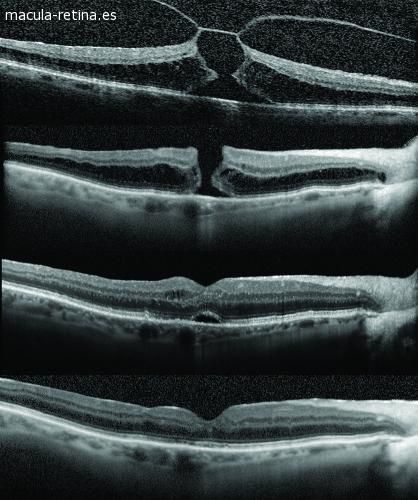

Bareiro explicó que el agujero maculares la presencia de una apertura en la mácula, que es la zona central de la retina.Detalló que existen dos tipos principales:el agujero macular idiopático y el agujero macular miópico.

Respecto al porqué se produce este caso, Bareiro precisó que “se produce por una atracción del vítreo, que es la sustancia gelatinosa que ocupa el 80% del contenido del globo ocular. Al contraerse, tira el centro de la retina hacia delante hasta producir un agujero en la zona correspondiente al centro de la visión, y una vez que se desarrolla el agujero macular, la posibilidad de que se cierre espontáneamente es muy pequeña”.

Nuestra oftalmóloga de confianza comentó que el tratamiento del agujero macular es quirúrgico: “las cirugías para estos casos generalmente, en un 95%, dan muy buen resultado, pero cuanto antes se realice la parte quirúrgica es mejor”.